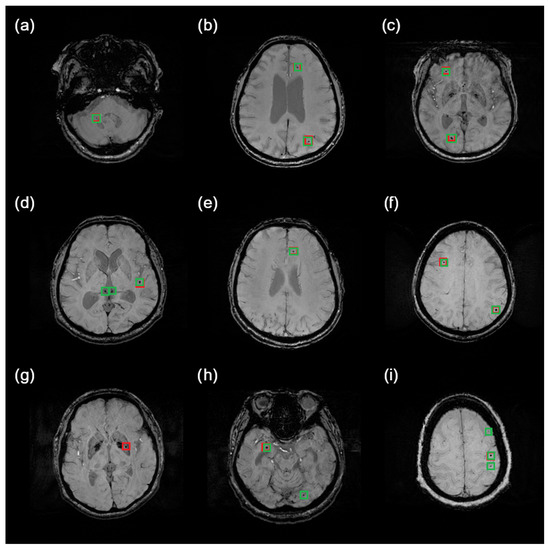

An example of how the system detects a microbleed is illustrated in Figure 6. The red boxes indicate ground truth CMBs, while the green ones represent system predictions. Although cerebral microbleeds are small lesions, the detector manages to find even hardly visible ones. It is also apparent that false-positive predictions are really similar to ground truth CMBs (see Figure 6d, for example).

Figure 6. Samples of results obtained by the proposed system. With red box there are marked Ground truth CMBs are marked with red boxes, while predicted CMBs are marked green. Images were intentionally brightened just for presentation purposes. Examples (ac,e,f) show correct predictions. Examples (d,h,i) show false-positive predictions. Example (g) shows a false-negative prediction.